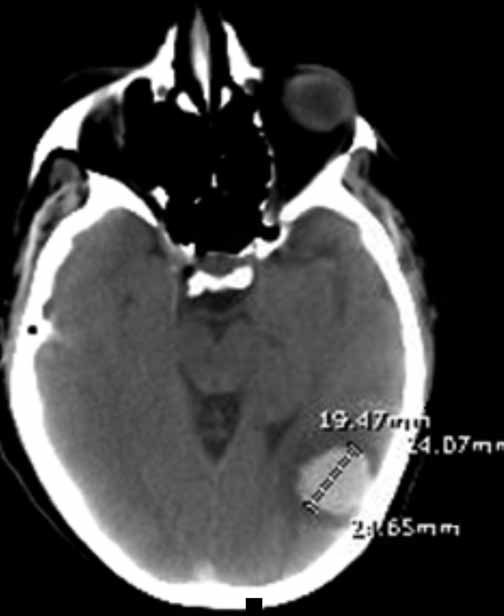

Dalia Hammoud, MD; Bout Rosel Haddad, MD; Georges El Homsy, MD

<p><img src="/sites/default/files/images/May_figA%26B_CTscan.jpg" style="margin-left: 8px; margin-right: 8px; float: left;" width="250" height="149">A...